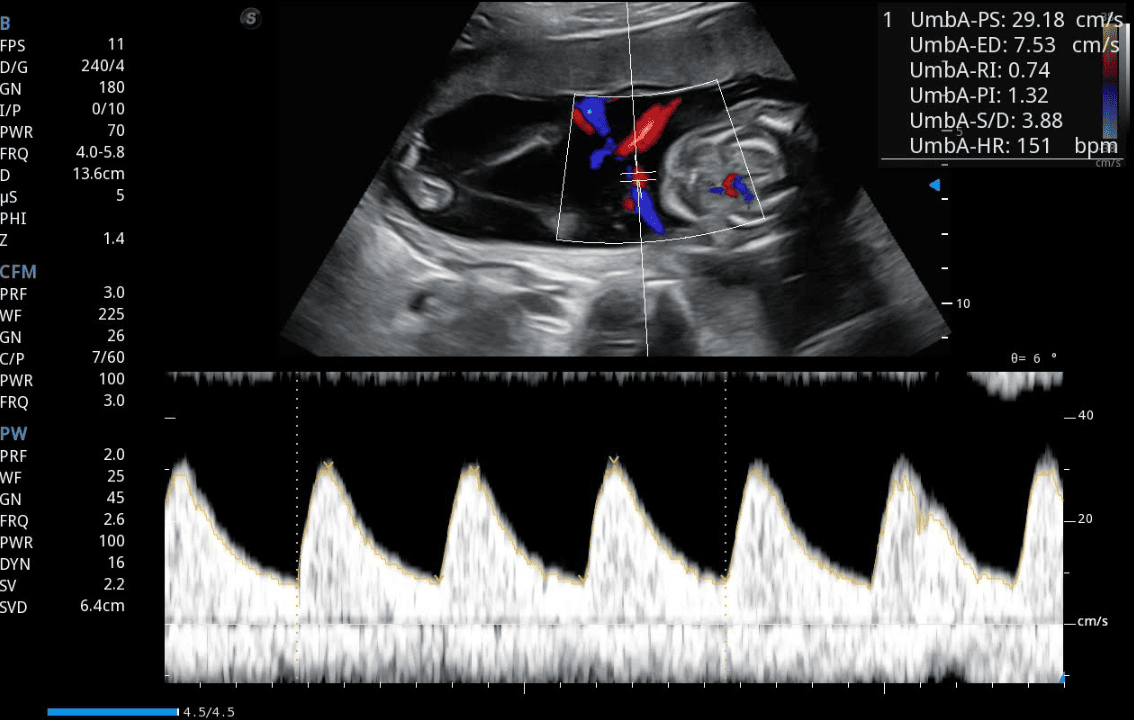

Arteria umbilical: indicador del intercambio placentario

La arteria umbilical transporta la sangre desoxigenada del feto hacia la placenta para su oxigenación. Mediante el Doppler, se pueden analizar los patrones de flujo en esta arteria para conocer el grado de resistencia placentaria.

Un flujo normal se caracteriza por una buena perfusión diastólica, lo que indica que la placenta permite el paso adecuado de sangre. En cambio, cuando existe aumento de la resistencia placentaria, el flujo diastólico disminuye o incluso se invierte, lo cual es un signo de insuficiencia placentaria y posible hipoxia fetal.

Índices de resistencia y pulsatilidad

Para cuantificar estos cambios, el especialista utiliza el Índice de Resistencia (IR) y el Índice de Pulsatilidad (IP).

• IR = (Velocidad sistólica – Velocidad diastólica) / Velocidad sistólica.

• IP = (Velocidad sistólica – Velocidad diastólica) / Velocidad media.

Valores elevados en cualquiera de estos índices indican que la placenta ofrece mayor oposición al flujo sanguíneo, lo que podría comprometer el desarrollo fetal.

Correlación clínica con patologías del embarazo

Un aumento sostenido del IR o IP suele asociarse con preeclampsia, hipertensión gestacional, diabetes y restricción del crecimiento intrauterino. En estos casos, el Doppler de la arteria umbilical se convierte en una herramienta indispensable para decidir si el embarazo puede continuar bajo vigilancia o si es necesario intervenir para proteger la vida fetal.